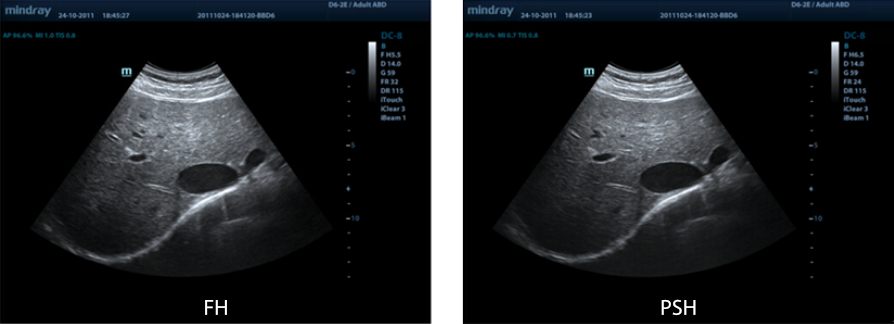

PSHI?(Phase Shift Harmonic Imaging)

Purified Harmonic Imaging for better contrast resolution providing clearer images with excellent resolution and less noise.